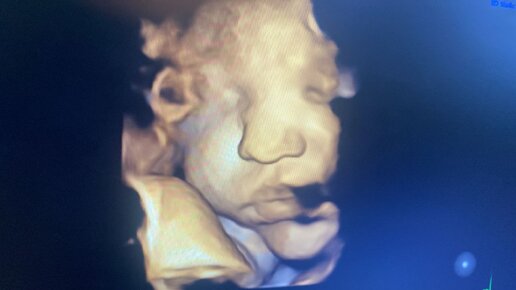

Иногда ребенок располагается к концу беременности в матке аномально, что может стать препятствием для самостоятельных родов. На протяжении беременности плод внутри полости матки много раз меняет свое положение, поворачиваясь то головкой, то ножками вниз. Относительно стабильное положение, которое сохранится уже до родов, он занимает примерно в 32-34 недели. Определенное положение малыша перед родами принято называть предлежанием. Особенности расположения крохи в матке и та часть, которая первой...